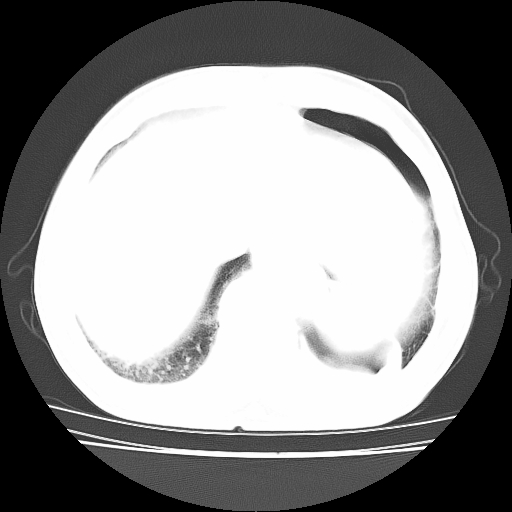

男,71岁,咳嗽,气喘10年,再发并咯血.胸片见气胸

考虑  左肺中心型肺癌伴阻塞性肺炎,肺不张,纵膈淋巴结肿大。慢支炎,肺气肿,左侧气胸肺压缩5%

1)考虑左肺中心型肺癌伴阻塞性肺炎、左肺下叶肺不张、左侧肺气肿,纵膈淋巴结转移。2)左侧气胸(肺组织压缩约5%)。

1)考虑左肺中心型肺癌伴阻塞性肺炎、左肺下叶肺不张、左侧肺气肿,纵膈淋巴结转移。2)左侧气胸。